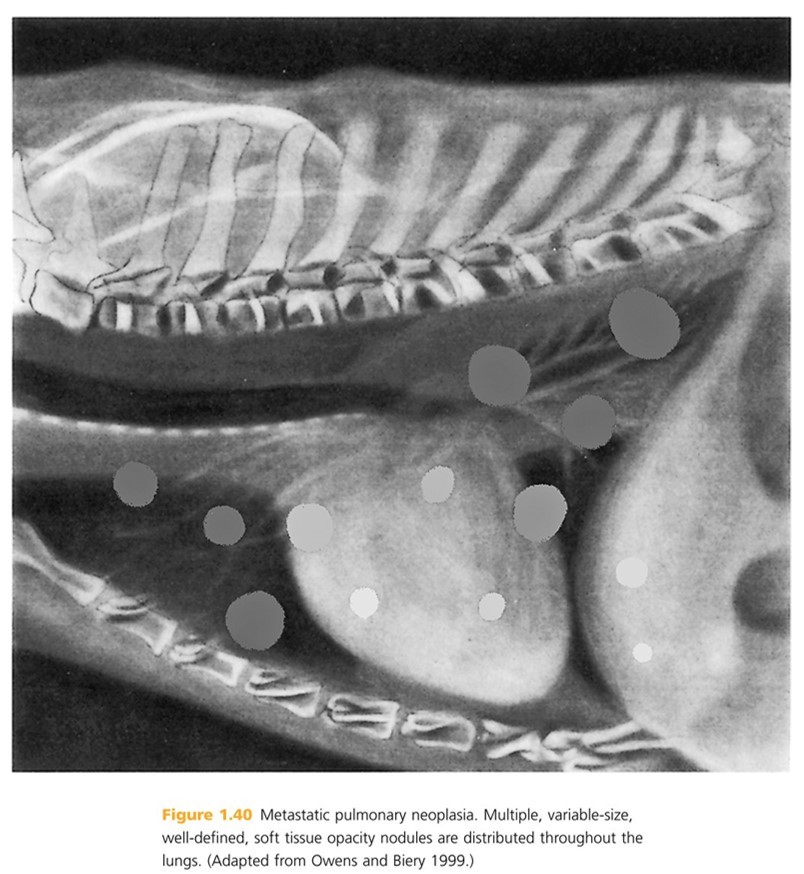

DDX for smooth-boareder, well defined nodules?`

Neoplasia (primary or mets)

Abscess

Granuloma

Fluid-containing bulla

Nodules are typically present as solid or nearly solid soft tissue structures, ______ from surrounding lung parenchya. It may be homogenous or heterogenous, be mineralize or cavitated (cavitated nodules may fill with gas or fluid). Gas (air) in a nodule may rsult from communication with an ______ or ____ _____.

distinct

airway or central necrosis